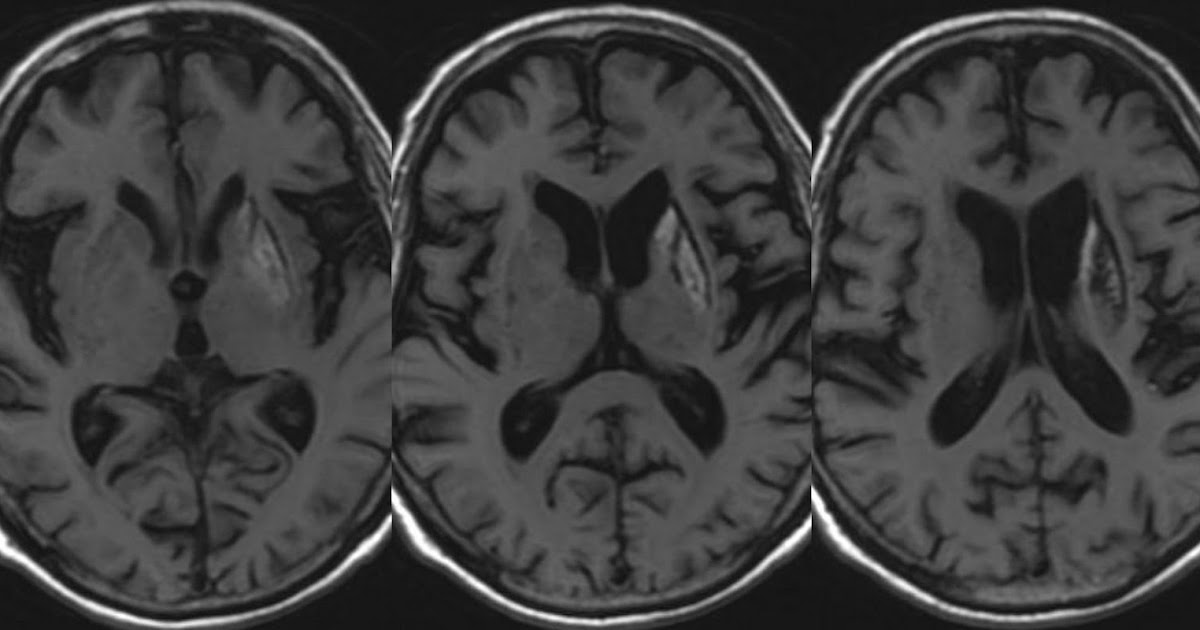

Figure 1 from Isolated symmetrical bilateral basal ganglia T2 Basal Ganglia T2 Hyperintensity The causes of basal ganglia t2 hyperintensity can be remembered using the mnemonic lint: If hemorrhage or mineral or protein. Mr spectroscopy with voxel sampling of the basal ganglia (. Marked t2 hyperintensity on flair within the dentate nuclei (a and b) and basal ganglia (c). Basal Ganglia T2 Hyperintensity.